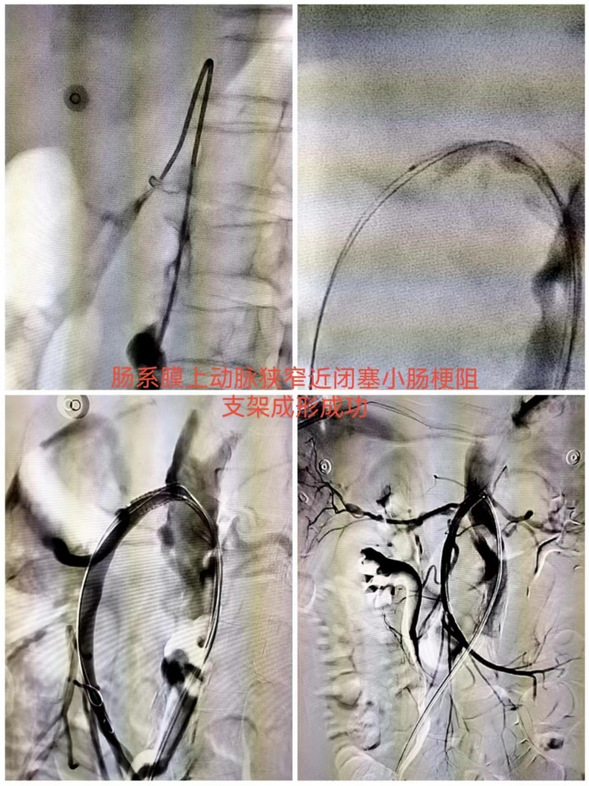

近日,患者孙某因腹痛,肛门停止排气排便就诊于我院普外科,普外科完善全腹CT提示肠梗阻,邀请介入科主任刘琳阅片及查体后考虑患者腹痛及肠梗阻不除外为肠系膜上动脉狭窄或栓塞导致,建议完善肠系膜上动脉CTA。患者完善检查后提示肠系膜上动脉狭窄。

经刘琳主任会诊后建议患者行肠系膜上动脉支架置入,患者及家属商议后同意,急诊给予肠系膜上动脉支架置入。

术后患者无明显腹痛,可正常饮食,可自行排气排便。术后复查肠系膜上动脉CTA提示支架通畅,肠系膜上动脉远端血供良好。